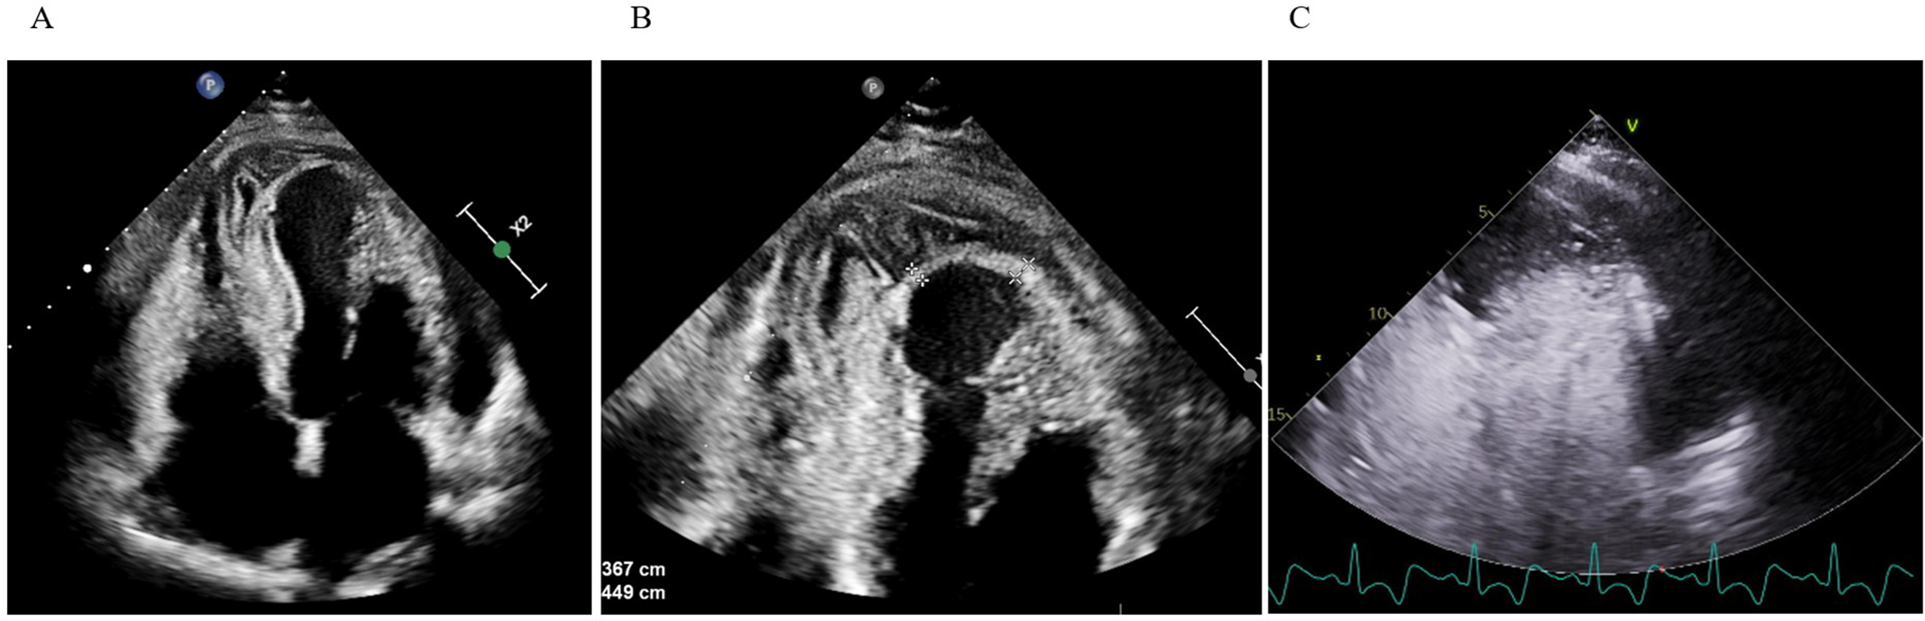

Initially diagnosed as stress-induced myocardial dysfunction, she was transferred back to a secondary hospital for further observation. Shortly thereafter, she became febrile (temperature up to 38.2°C) and was treated with oral penicillin for streptococcal pharyngitis. Despite therapy, inflammatory markers (CRP 192 mg/L) remained high, and troponin rose to 4,584 ng/L. TTE on September 16 demonstrated a moderately dilated LV [end-diastolic diameter (EDD) 60 mm], dyskinesia of the apical segments of the LV, mild pericardial effusion, and suspicious “layering” in the LV wall consistent with intramyocardial bleed or pseudoaneurysm (Figure 1).

Figure 1

Transthoracic echocardiography. (A,B) Apical four-chamber view shows apical and inferoseptal myocardial thickening with a large, echolucent, spindle-shaped intramyocardial cavity, without evident communication to cardiac chambers or pericardial space. (C) Contrast echocardiography demonstrates no flow from the ventricular cavity into the lesion.